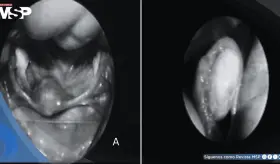

El paciente acudió dos meses después de lo programado para extracción del stent, encontrándose con una incrustación significativa y anudamiento de la punta superior en pelvis renal izquierda.